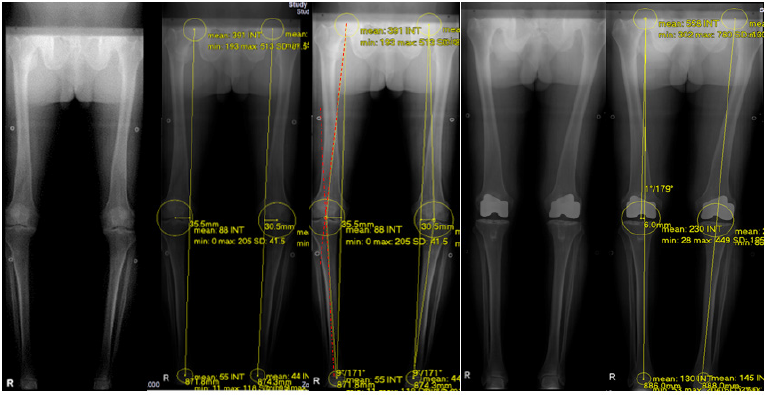

Figure 4: The pre-op and post-op measurements of the Mechanical axis line using the Hip Knee Ankle scanogram. The dotted red line denotes the Mechanical Axis Deviation Angle (MAD).

On the Hip Knee Ankle scanogram, a straight line is drawn from the center of the femoral head to the center of the ankle. This line is away from the center of the knee and this distance (mm) is measured in both varus and valgus knees. Also, the degree of deviation of this line, from the center of the knee is measured and categorized as Neutral if it passed through the center, or varus and valgus outlier. The degree of correction, or the accuracy of the FMA finder is then measured 2 months after Axis Total Knee Replacement in standing HKA scanogram, measuring how close the line was to the center of the knee. Our goal is to bring the line in neutral or within the 3 degrees of varus and valgus outliers. Similarly, the preoperative mechanical axis deviation angle (MAD) was compared to the postoperative MAD to measure the degree of deformity correction. Mechanical axis deviation angle was measured using the center of the femoral head to the center of the knee and center of the tibial spine to the center of the ankle joint (using the femoral and tibial mechanical axis line). Implant position either in flexion or extension was measured in lateral view and patellar tracking was measured in Laurin view. Measurement was done by two individual orthopedic surgeons in fellowship training. The author was one of the readers (Reader 1) and measurement was repeated every 2 months after to look at the intra-observer reliability (Figure 4; Table 7-10).